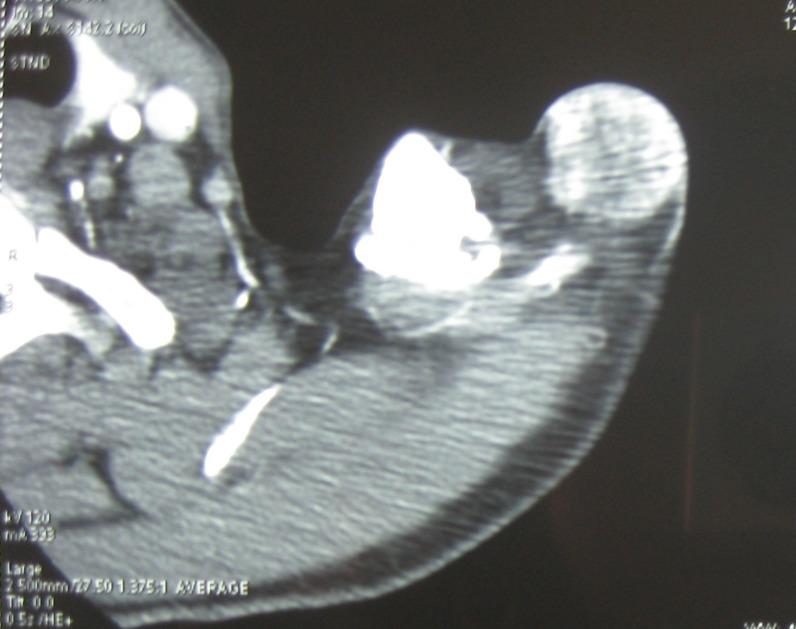

We present a case of subcutaneous Ewing sarcoma within the left shoulder of a 49-year-old man, without osseous involvement. Physical examination suggested a vascular tumor. Histologically, it was a small round cell tumor that marked strongly for CD99. The diagnosis of subcutaneous Ewing sarcoma was performed.

我们报告一例49岁男性左肩皮下尤文肉瘤,无骨质受累。体格检查提示为血管性肿瘤。组织学上,它是一种小圆形细胞肿瘤,CD99染色强阳性。诊断为皮下尤文肉瘤。